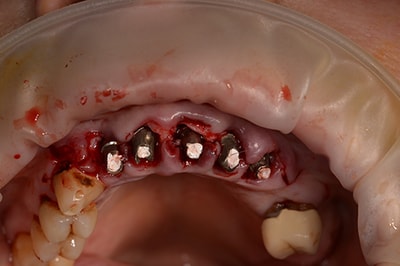

Chirurgie Guidée

L’implantologie moderne évolue vers un positionnement des implants dicté par la prothèse. Il permet et garantit un meilleur résultat esthétique, une meilleure distribution des forces et une hygiène facilitée. La combinaison de l’imagerie 3D et de logiciels de planification autorise des études préliminaires d’une grande finesse. On pourra ainsi visualiser la faisabilité prothétique d’un plan de traitement implantaire.

Au cabinet, pour les cas complexes, après réalisation d’une imagerie 3D (scanner ou cone beam), le cas sera étudié (avec un logiciel de planification), et une solution sera proposée. Dès validation, un guide chirurgical sera confectionné, dans l’absolu respect de la planification. Il permettra de positionner et placer chaque implant dans la position et l’axe pré-défini.

Plusieurs types de guides sont possibles. S’il reste des dents sur l’arcade, nous réaliserons un guide dento-porté (stable et précis). S’il ne reste aucune dent, nous devrons réaliser un guide ostéo-porté.

Ce type d’intervention permet au patient, de repartir le jour de l’intervention, avec une solution esthétique et fonctionnelle.